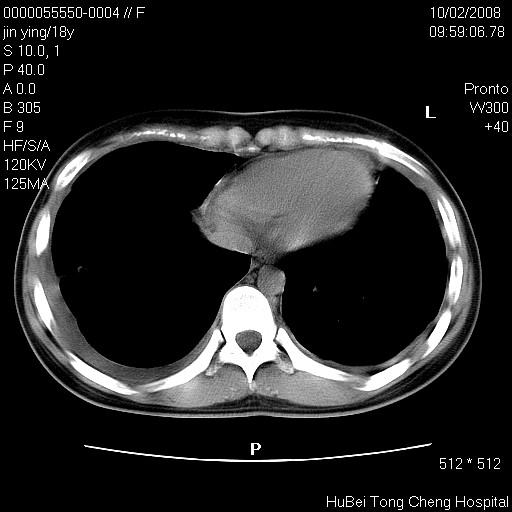

患者 女,18y。发热十余天,伴咳嗽。pe:t39⒈℃,bp 110/80mmhg,p 86次/min。神清,精神欠佳。双肺可闻及少许湿罗音。既往史不详。

临床诊断:肺部感染?

胸部ct轴位平扫(层厚10mm,螺距1.5,重建间隔10mm),图像如下: